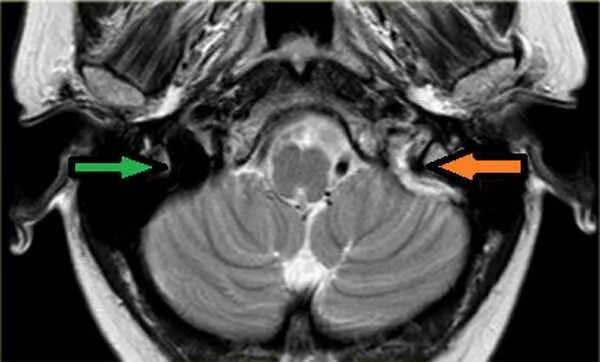

Синусы мозга мрт